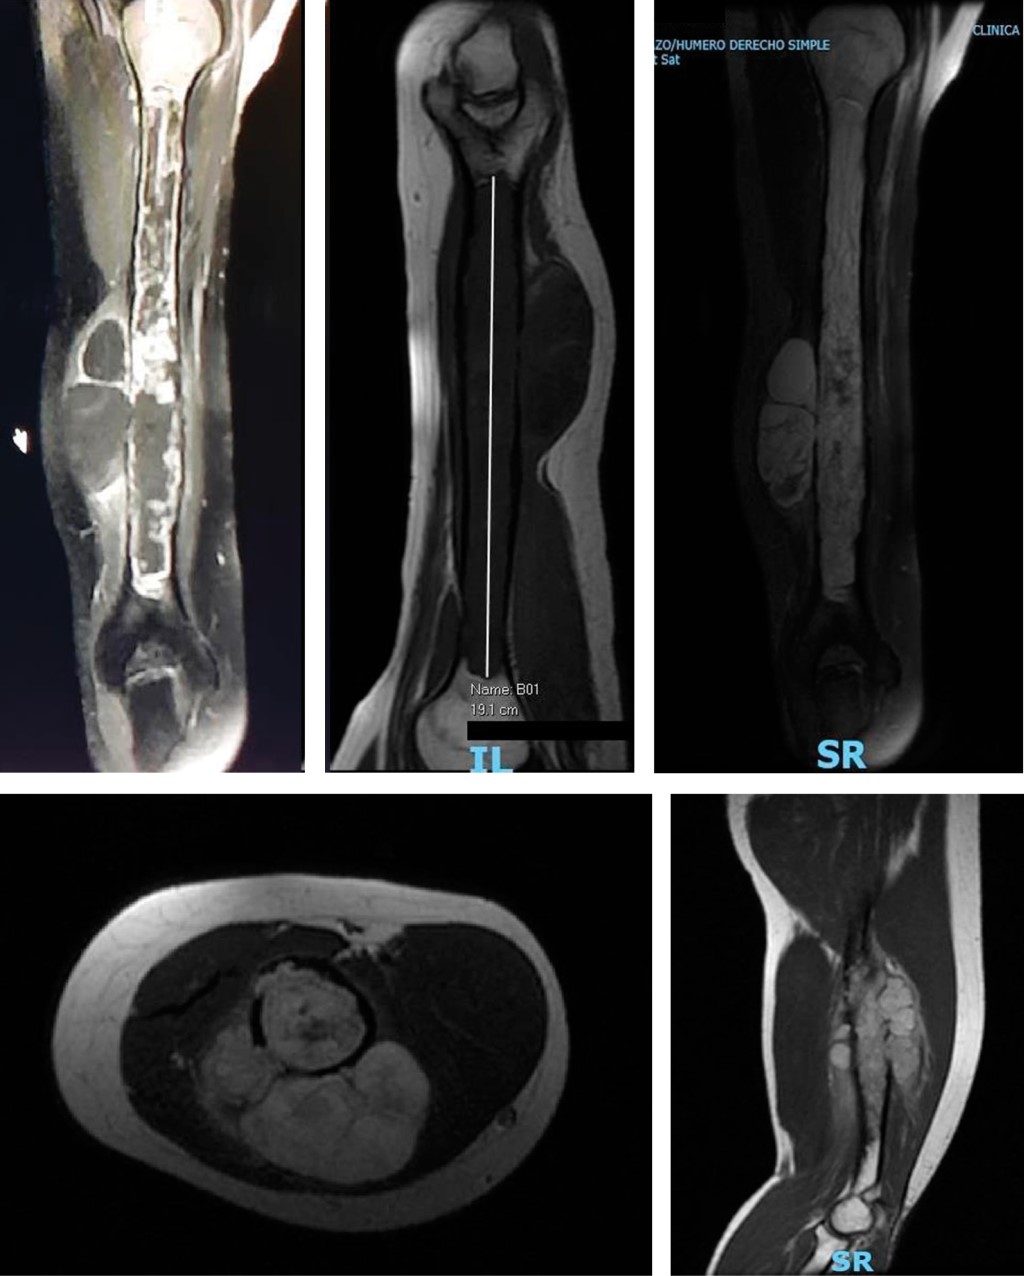

Contrast-enhanced MRI showed an infiltrative, diffuse endosteal lesion affecting the humeral shaft extending 19 cm longitudinally from the humeral neck to the supracondylar region, infiltrating and destroying the cortex in the lateral margin of the middle third of the diaphysis. The scan also revealed a soft tissue mass involving the deep muscle groups on the posterolateral aspect of the arm that measured approximately 7.8 × 4.9 × 2.6 cm in diameter (lateral1anteroposterior1transverse). The tumor signal was predominantly high on the T2 sequences, with hemorrhagic content and a focal juxtacortical tumor component toward the posterior and medial margins measuring 2.4 cm and presenting with marked diffusion restriction and contrast enhancement, suggesting a large tumor component in this segment. Peripheral enhancement of the tumor lesion was also observed, and there were no displaced or angled fractures. Tumor involvement was not observed in the proximal or distal epiphysis of the humerus. The humeral vascular bundle running along the medial aspect of the arm did not demonstrate signs of tumor infiltration, but branches supplying the tumor were observed emerging from the distal brachial artery.

The dimensions for surgical planning were confirmed on MRI following an assessment of bone extension and soft tissue involvement on the different planes (Figure 2).

Figure 2